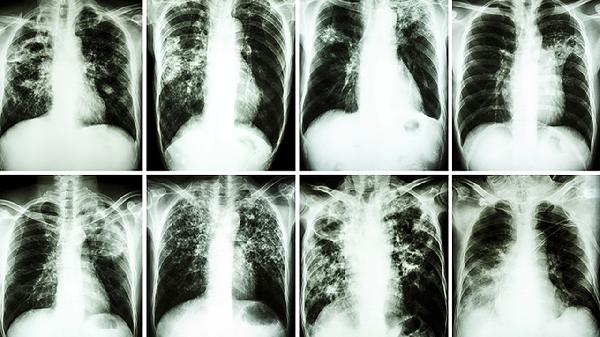

肿瘤标志物升高可能反映病灶活动,但也可能是非肿瘤因素引起。例如,感染或炎症时体内炎症反应可能导致数值波动;治疗过程中肿瘤细胞破坏也可以短暂升高标志物水平。器官功能变化(如肝病、肾病)可能干扰标志物代谢,导致异常数值。这些都需要综合影像学检查、病史、临床症状等信息共同评估。